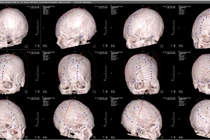

Bệnh viện đa khoa Phú Thọ vừa phẫu thuật tạo hình bằng lưới titan 3D thành công ghép sọ cho người bệnh bị tiêu xương sọ, hộp sọ biến dạng sau phẫu thuật ghép xương tự thân.